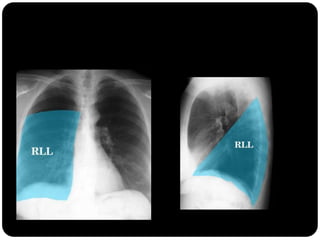

Pulmões – lobos - fissuras

 Direito: 3 lobos (fissura oblíqua = maior e a horizontal =

menor)

 Esquerdo : 2 lobos (fissura oblíqua)

 Pulmão direito:

 LSD: anterior, apical e posterior;

 LM: medial e lateral;

 LID: superior, basal medial, basal lateral,

basal anterior, basal posterior;

 Pulmão esquerdo:

 LSE: apicoposterior, anterior,

superior(língula), inferior(língula);

 LIE: segmento superior, basal antero-

medial, basal lateral e basal posterior;